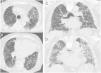

“UIP”: Honeycombing must be present; it can be seen with or without traction bronchiectasis (Fig. 1). The typical distribution of UIP is subpleural with basal predominance, although some upper lobe involvement is common. Mediastinal lymphadenopathy may be present in patients with UIP. Ground-glass opacification may be present, but it is not a dominant feature and is usually accompanied by a superimposed reticular pattern.

“Probable UIP”: Subpleural, basal-predominant reticular abnormalities with peripheral traction bronchiectasis or bronchiolectasis (Fig. 2). As with a UIP pattern, ground-glass opacification may be present in probable UIP, but it is not a dominant feature.

Figure 2.CT images with the features of probable UIP pattern. (A) displays subleural predominant interstitial changes without clear honeycombing. The coronal reformatted image (B) shows the apicobasal gradient of the pulmonary changes. Also traction bronchiectasis are present, also mild ground glass opacification.